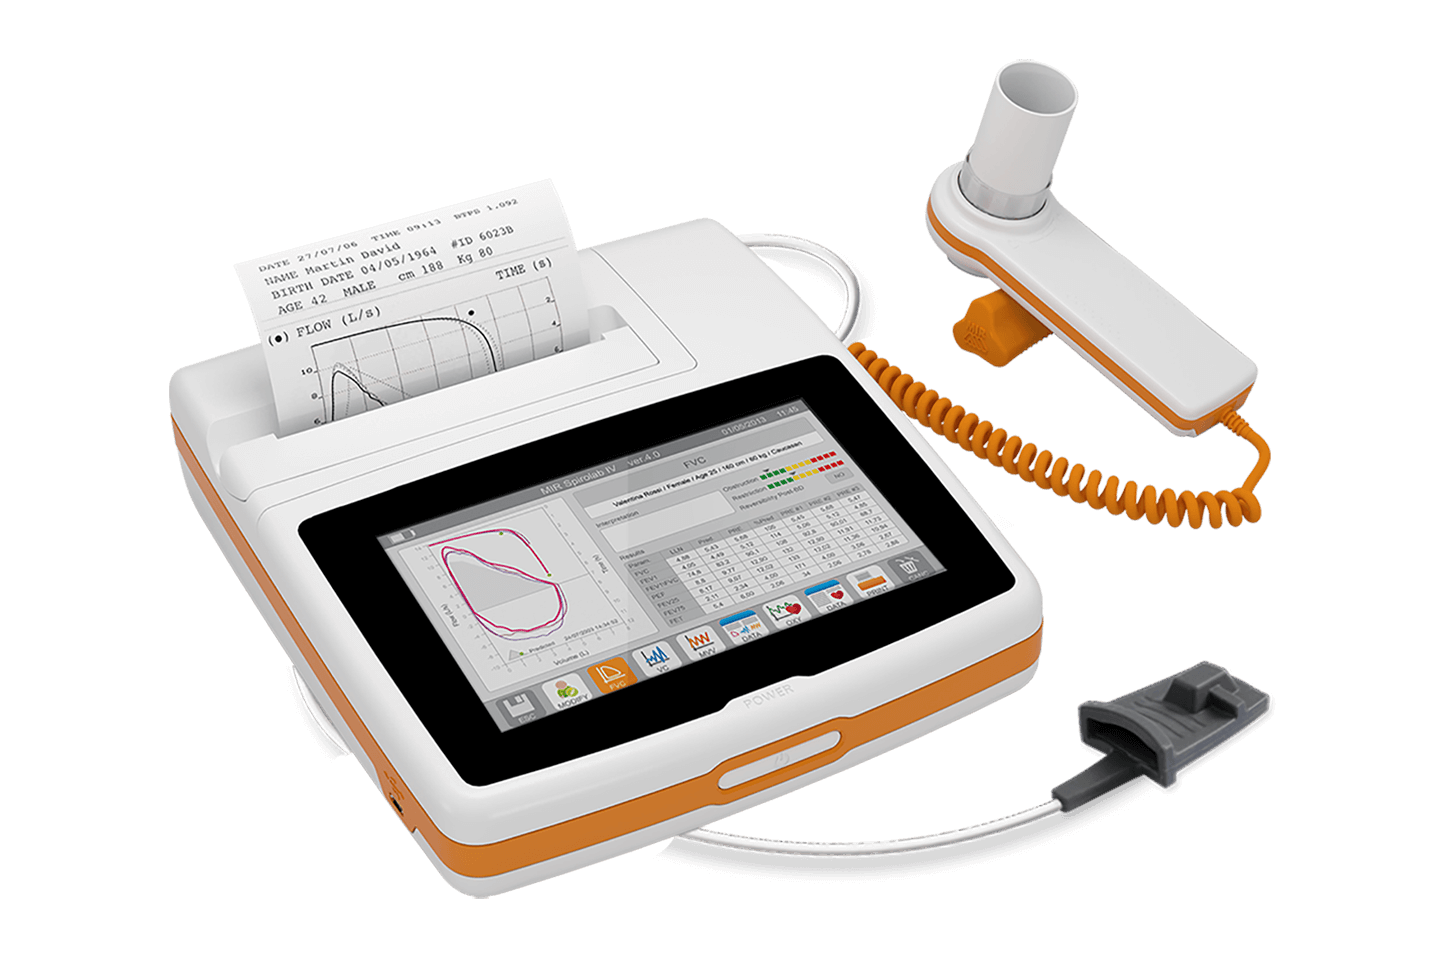

Helios 702 Portable Spirometer - INDIA

Helios 702 Portable Spirometer - INDIA

SP100B SPIROMETER

SP100B SPIROMETER

SP80B SPIROMETER

SP80B SPIROMETER

Medikro ® Pro Laboratory Spirometer

Medikro ® Pro Laboratory Spirometer

Medikro ® Duo - The 2 minute asthma and COPD screener

Medikro ® Duo - The 2 minute asthma and COPD screener

SPIROMETER SPIROLAB

SPIROMETER SPIROLAB

Spirometer handheld Mini spir Light MIR/Italy

Spirometer handheld Mini spir Light MIR/Italy